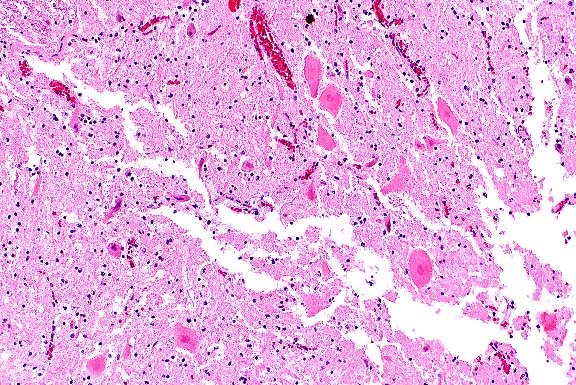

- Case 18-1. Lung. Note intimal and medial hyperplasia

of small arteries which nearly or completely occlude the lumens.

The adjacent interstitium is expanded by lymphocytes, anthracotic

pigment, and cell debris.

- AFIP Diagnosis: Lung: Arteriopathy, plexiform, multifocal,

moderate, with diffuse congestion and multifocal alveolar edema,

Maltese, canine.

Note: Some sections may contain minimal acute interstitial

inflammation associated with bacilli.

- Conference Note: Pulmonary hypertension induces a

spectrum of vascular lesions in the lung, some of which have

characteristic microscopic features with diagnostic significance.

Although vessel changes may involve the entire arterial tree,

the lesions are most prominent in arterioles and small arteries.

The lesions of the pulmonary vasculature in this Maltese puppy

are characterized by multifocal medial hypertrophy of small to

medium-sized arterioles, loss of the internal elastic lamina,

and extensive hyperplasia of the tunica intima that narrows or

occludes vessel lumens. Occasionally, the hyperplastic endothelium

forms tufts of small, glomerulus-like, capillary channels that

span the lumens of dilated arterioles, resembling a network or

web (hence, plexogenic pulmonary arteriopathy). Multifocally,

there is fibrosis of the alveolar interstitium.